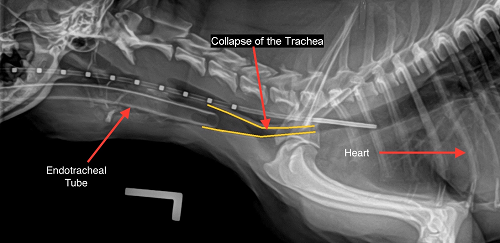

X-rays

are the quickest and least expensive method of detecting a

collapsing trachea. (See x-ray at right from the

Univ. of Missouri.)

Fluoroscopy (or videofluoroscopy), which shows a continuous x-ray image, so that the trachea can be viewed in motion upon inhaling and exhaling, can confirm tracheal collapse. The dog is awake during this procedure, although it may be sedated. Computed tomography (CT) scans can assess structural abnormalities in the trachea. Other methods include ultrasound and tracheobronchoscopy.